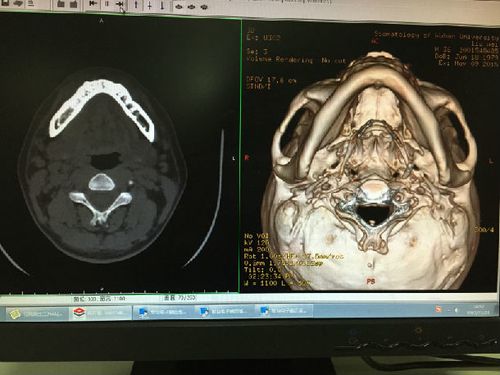

颌下腺大小约2.0 × 3.4 cm,呈三角型或类圆型.

刘某,男,36岁,右侧颌下腺导管结石,ct片可见右侧口底前份,以及靠近

颌下腺导管结石ct图片